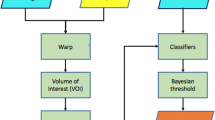

Alzheimer’s disease (AD) is an irreversible, progressive, and ultimately fatal brain degenerative disorder, no effective cures for it till now. Despite that, the available treatments can delay its progress. So, early detection of AD plays a crucial role in preventing and controlling its progress. Hippocampus (HC) is among the first impacted brain regions by AD. Its shape and volume are measured using a structural magnetic resonance image (MRI) to help AD diagnosis. Therefore, brain hippocampus segmentation is the building block for AD detection. This study’s main objective is to propose a deep learning Alzheimer’s disease hippocampus segmentation framework (DL-AHS) for automatic left and right hippocampus segmentation to detect and identify AD. The proposed DL-AHS framework is based on the U-Net architecture and estimated on the baseline coronal T1-weighted structural MRI data obtained from Alzheimer’s disease neuroimaging initiative (ADNI) and neuroimaging tools and resources collaboratory (NITRIC) datasets. The dataset is processed using the Medical Image Processing, Analysis, and Visualization (MIPAV) program. Besides, it is augmented using a deep convolutional generative adversarial network (DC-GAN). For left and right HC segmentation from other brain sub-regions, two architectures are proposed. The first utilizes simple hyperparameters tuning in the U-Net (SHPT-Net). The second employs a transfer learning technique in which the ResNet blocks are used in the U-Net (RESU-Net). The empirical results confirmed that the proposed framework achieves high performance, 94.34% accuracy, and 93.5% Dice similarity coefficient for SHPT-Net. Also, 97% accuracy and 94% Dice similarity coefficient are achieved for RESU-Net.